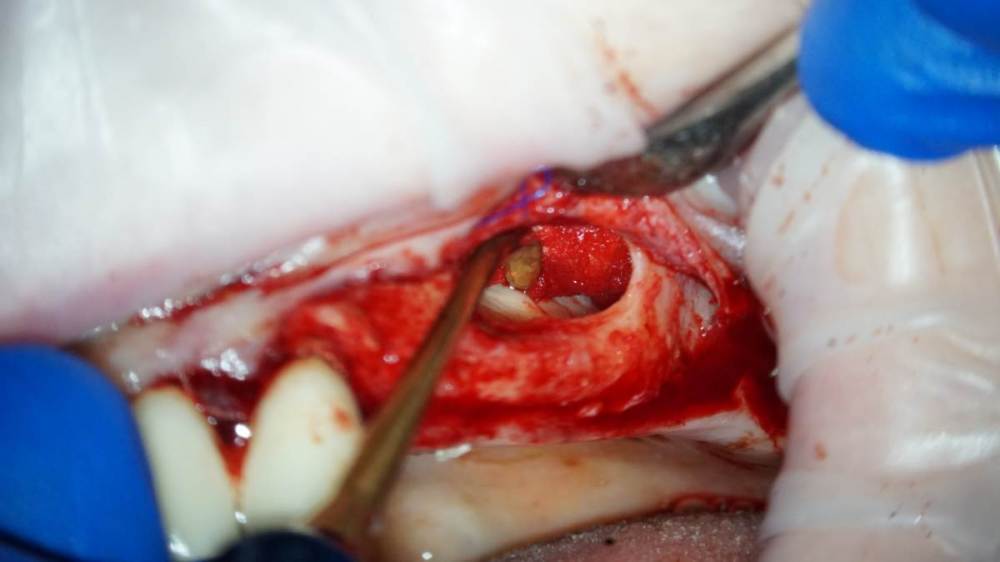

TIGER Опубликовано 18 февраля, 2022 Поделиться Опубликовано 18 февраля, 2022 Приветствую коллеги!Небольшой кейс с удалением кисты и синусом.Произведено :удаление кисты,синус-лифт ,через 4 месяца имплантация,ещё через 4 протезирование 5 1 1 Ссылка на комментарий